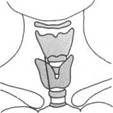

железы при поперечном сканировании.

Поперечные размеры составляют 30x20 мм, высота - 30-40 мм.

HU.

13 26 4.1 16

8 15 13 26 41 18 16